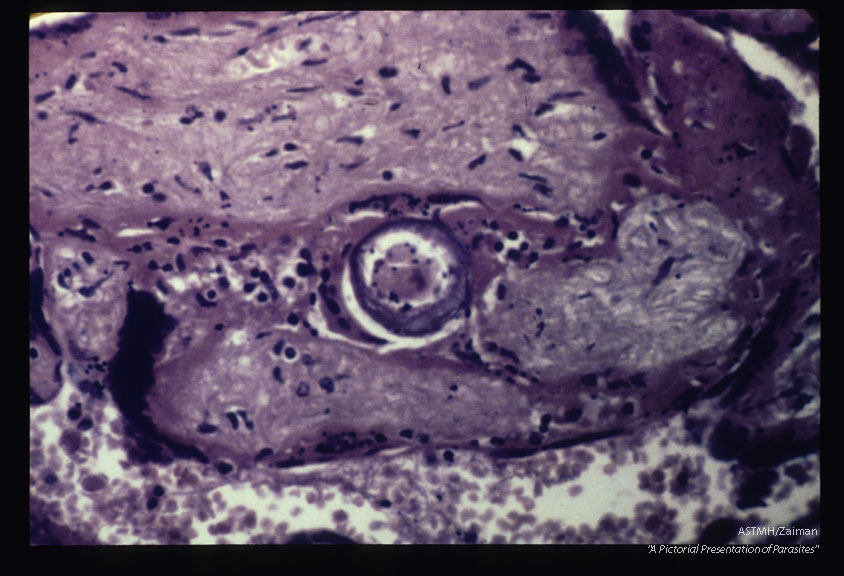

Schistosomal placentitis. An egg is present among the villi. Note disappearance of the trophoblastic epithelium.

Description: Schistosomal placentitis. An egg is present among the villi. Note disappearance of the trophoblastic epithelium.